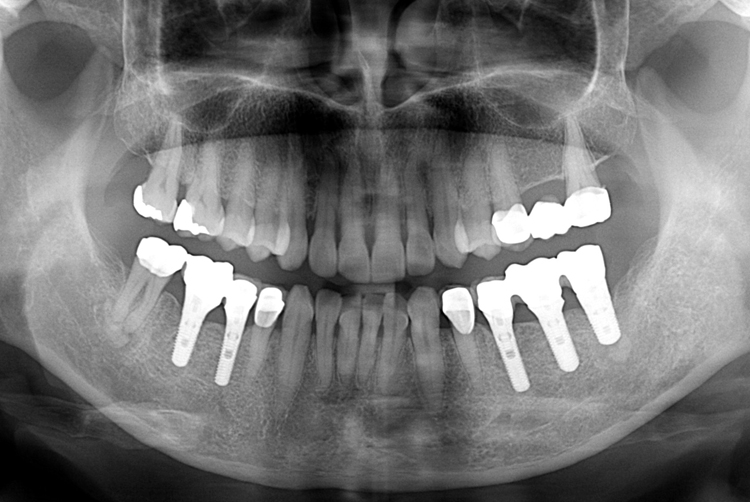

치료사례

세종치과의 진심 어린 치료는 결과로 말합니다.

실제 내원하신 환자분들의 치료 전·후 사례를 확인해보세요.

모든 치료사례 전후사진은 환자분의 동의하에 촬영되었습니다.

모든사진은 동일 환자분의 전후모습을 촬영하였으며, 사진의 밝기조절 외에 임의 수정이 없음을 알려드립니다.